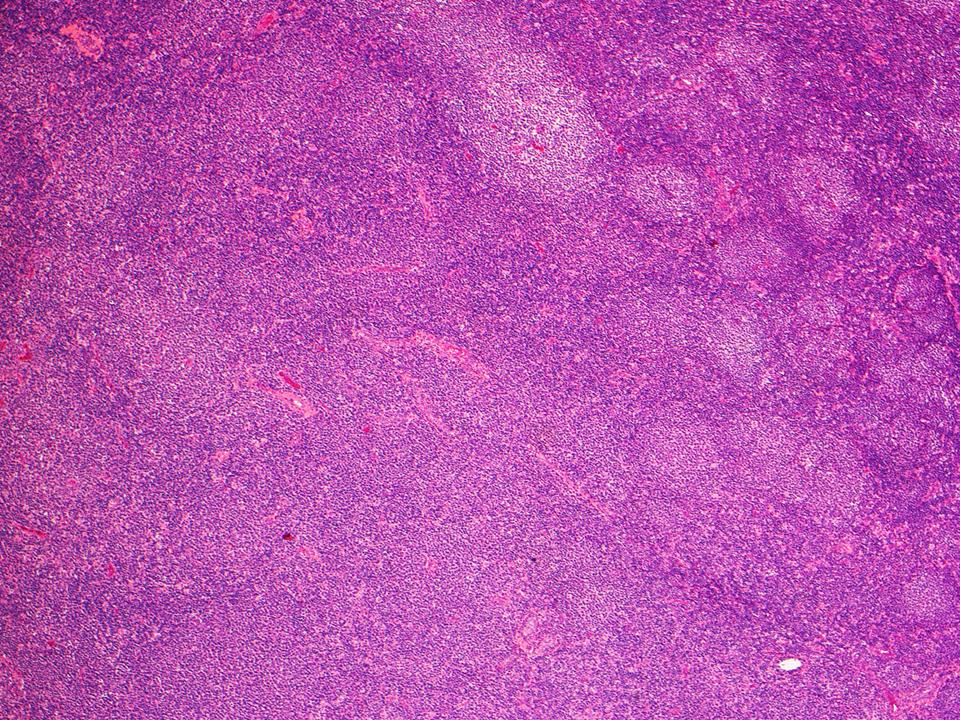

Mantle cell lymphoma

Mantle cell lymphoma 115 фотографий